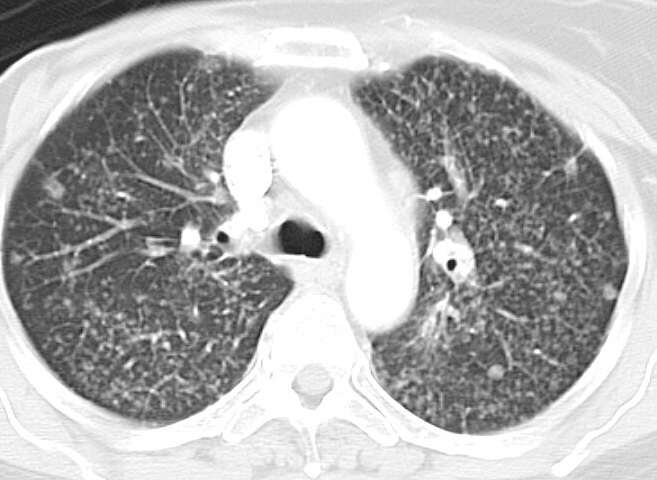

Gallery Lung Cancer Mets breast 1 CT

breast 1 CT